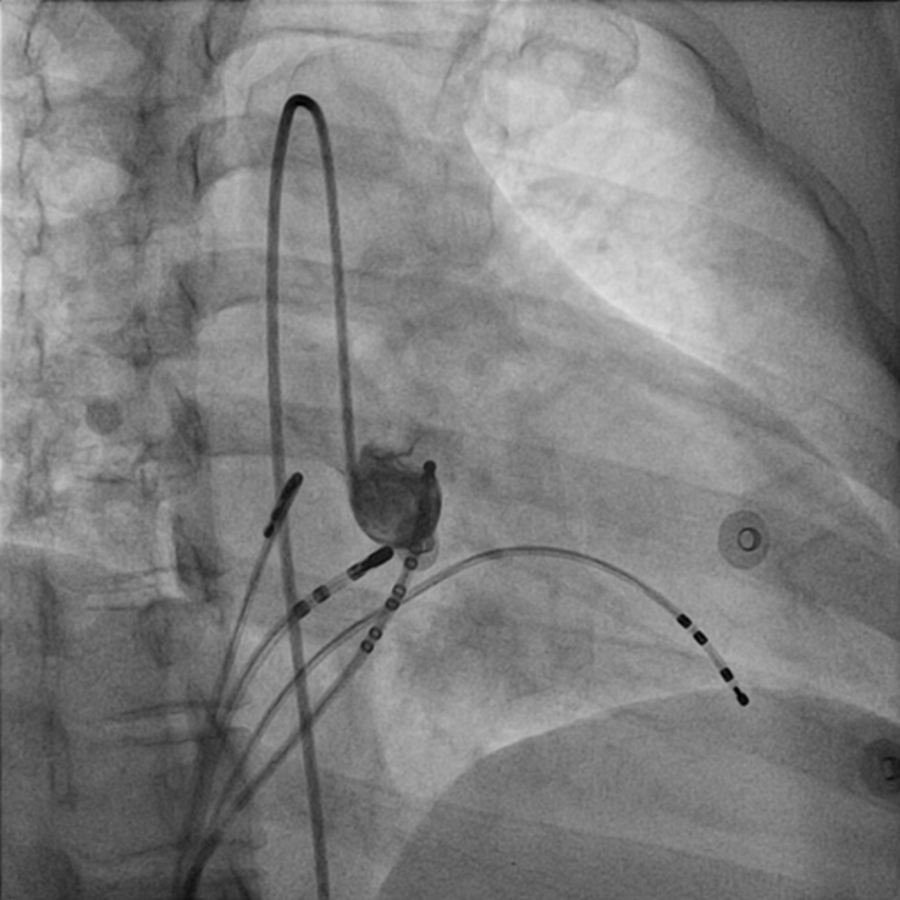

Ablation catheter in NCC

03_abl_site00001.jpg